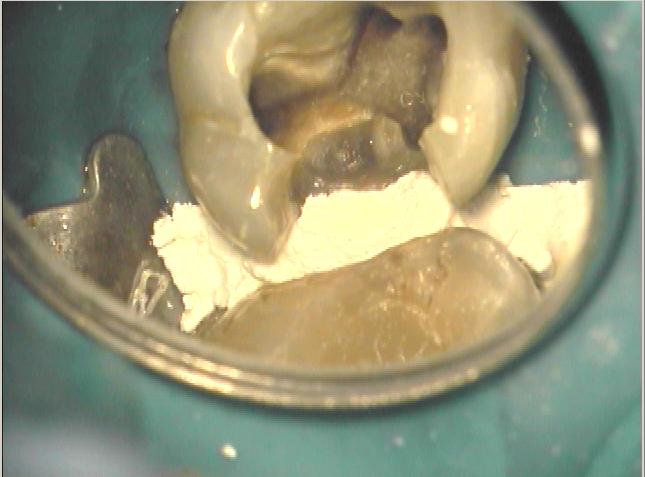

Klinische Ausgangssituation

Klinische Ausgangssituation zur gleichen Zeit

Zustand unmittelbar vor Behandlungsbeginn

Zustand unmittelbar vor Behandlungsbeginn im Juni 2003. Die Fraktur des distalen Zahnanteils hat die Patientin jetzt zur Einwilligung in die Behandlung motiviert. Auffällig ist in dieser Projektion die besonders starke Krümmung der mb Wurzel sowie die knochennahe Defektlage distal. Es erfolgte zunächst die Kariesentfernung gefolgt von einer chirurgischen Kronenverlängerung zur Herstellung der biologischen Breite sowie Ermöglichung des sog. Ferrule-Effektes. Danach wurde der Zahn adhäsiv aufgebaut. Erst jetzt wurde mit der eigentlichen WKB begonnen